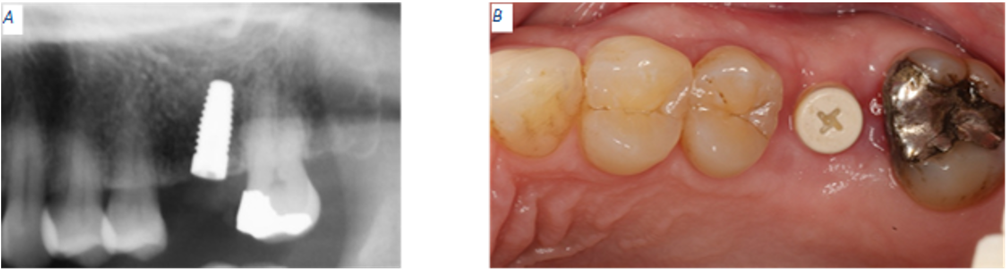

Four months after receiving final implant crown

Patient presents for an emergency dental visit four months after the implant supported, cement retained crown was delivered for site #14. The patient’s CC is that she feels that her implant is loose, but she does not have any pain or bleeding. Patient reports that a few weeks ago she heard a crunch while eating a breakfast sandwich but there was no apparent mobility or pain at that time. Intraoral evaluation reveals mobility of the implant crown. Periapical radiograph confirms a catastrophic implant fracture (Fig 6).

Figure 6: Abrupt fracture of zirconia implant.

Figure 7: Patient retrieved piece of implant attached to crown.

The prosthodontist offered to remove the broken implant piece to reduce the chances of swallowing or aspirating the loose part, but the patient refused. She agreed to consult with the oral surgeon and settled into going back to the OR to have the loose implant piece removed and receive a bone graft to cover the osseointegrated apical piece while at the same time reducing the chance of developing a major crestal ridge defect. The patient and the prosthodontist discussed the possibility of replacing missing tooth #14 with a three-unit FPD, but the patient refused this kind of treatment. A few days later, the patient returned to the dental clinic with the coronal portion of the fracture implant and the implant crown in her hand (Fig 7).